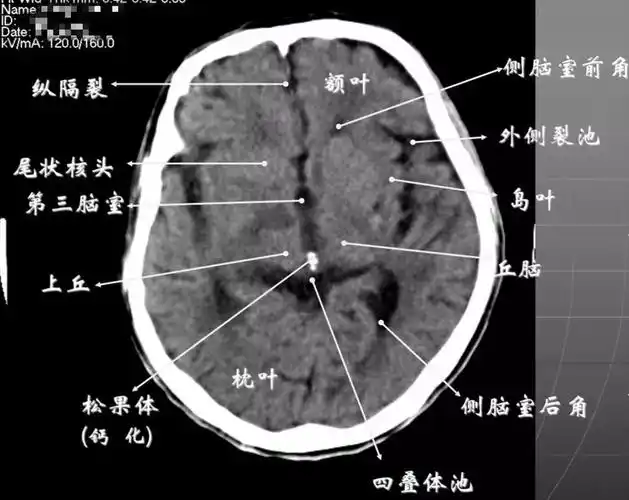

读懂头颅ct并不难,教你成为读片小能手